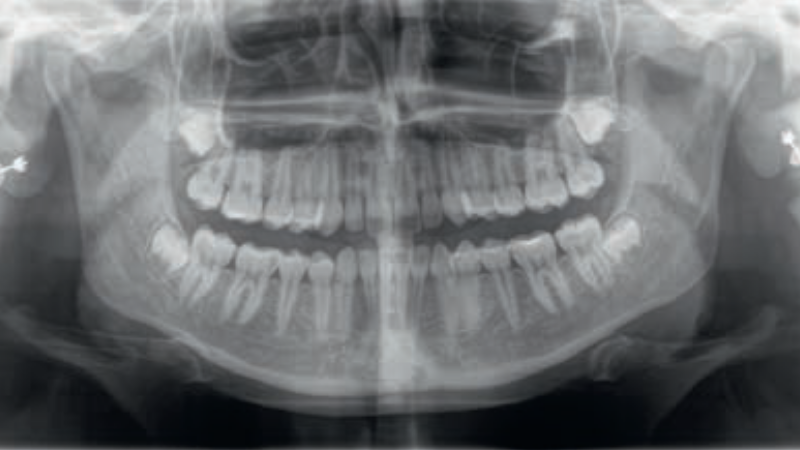

Streszczenie: Martwicza sialometaplazja (necrotizing sialometaplasia, NS) jest rzadką, łagodną i samoograniczającą się jednostką chorobową, obejmującą najczęściej drobne gruczoły ślinowe podniebienia. Jej obraz kliniczny i histopatologiczny może imitować zmiany nowotworowe, w szczególności raka płaskonabłonkowego oraz raka śluzowo-naskórkowego, co istotnie utrudnia prawidłowe rozpoznanie i może prowadzić do wdrożenia nadmiernie agresywnego leczenia. Etiologia NS pozostaje nie do końca poznana, jednak za kluczowy mechanizm patogenetyczny uznaje się miejscowe niedokrwienie tkanek gruczołowych. Celem pracy było przedstawienie opisu przypadku martwiczej sialometaplazji u młodej pacjentki oraz omówienie jej charakterystyki kliniczno-patologicznej, ze szczególnym uwzględnieniem diagnostyki różnicowej. Osiemnastoletnia pacjentka zgłosiła się z powodu silnego bólu podniebienia. W badaniu klinicznym stwierdzono obustronne wygórowania błony śluzowej podniebienia twardego oraz kraterowate owrzodzenie. Wstępna diagnostyka różnicowa obejmowała proces nowotworowy. Wykonano biopsję zmiany, a badanie histopatologiczne wykazało metaplazję płaskonabłonkową przewodów gruczołów ślinowych, ogniska martwicy komórek pęcherzykowych, wynaczynienie śluzu oraz naciek zapalny, przy zachowanej architekturze zrazikowej, co pozwoliło na ustalenie rozpoznania NS. Zastosowano postępowanie zachowawcze. W trakcie obserwacji odnotowano stopniową regresję zmian, a dolegliwości [...]